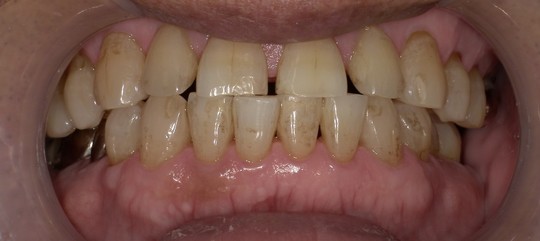

年齢:70代男性

治療内容:エアーフローによる歯の着色汚れ、ステイン除去

治療期間/通院回数:1回

費用: ステインコース 8,800円

リスク・副作用

①効果には個人差があり、着色汚れによっては一度に取りきれない場合があります。

施術後数時間以内に、着色効果の強いもの(コーヒー・紅茶・喫煙など)を摂取すると、歯に色素沈着が起こる可能性があります。

パウダーの刺激により歯ぐきから出血する可能性があります(痛みはほとんどありません)。